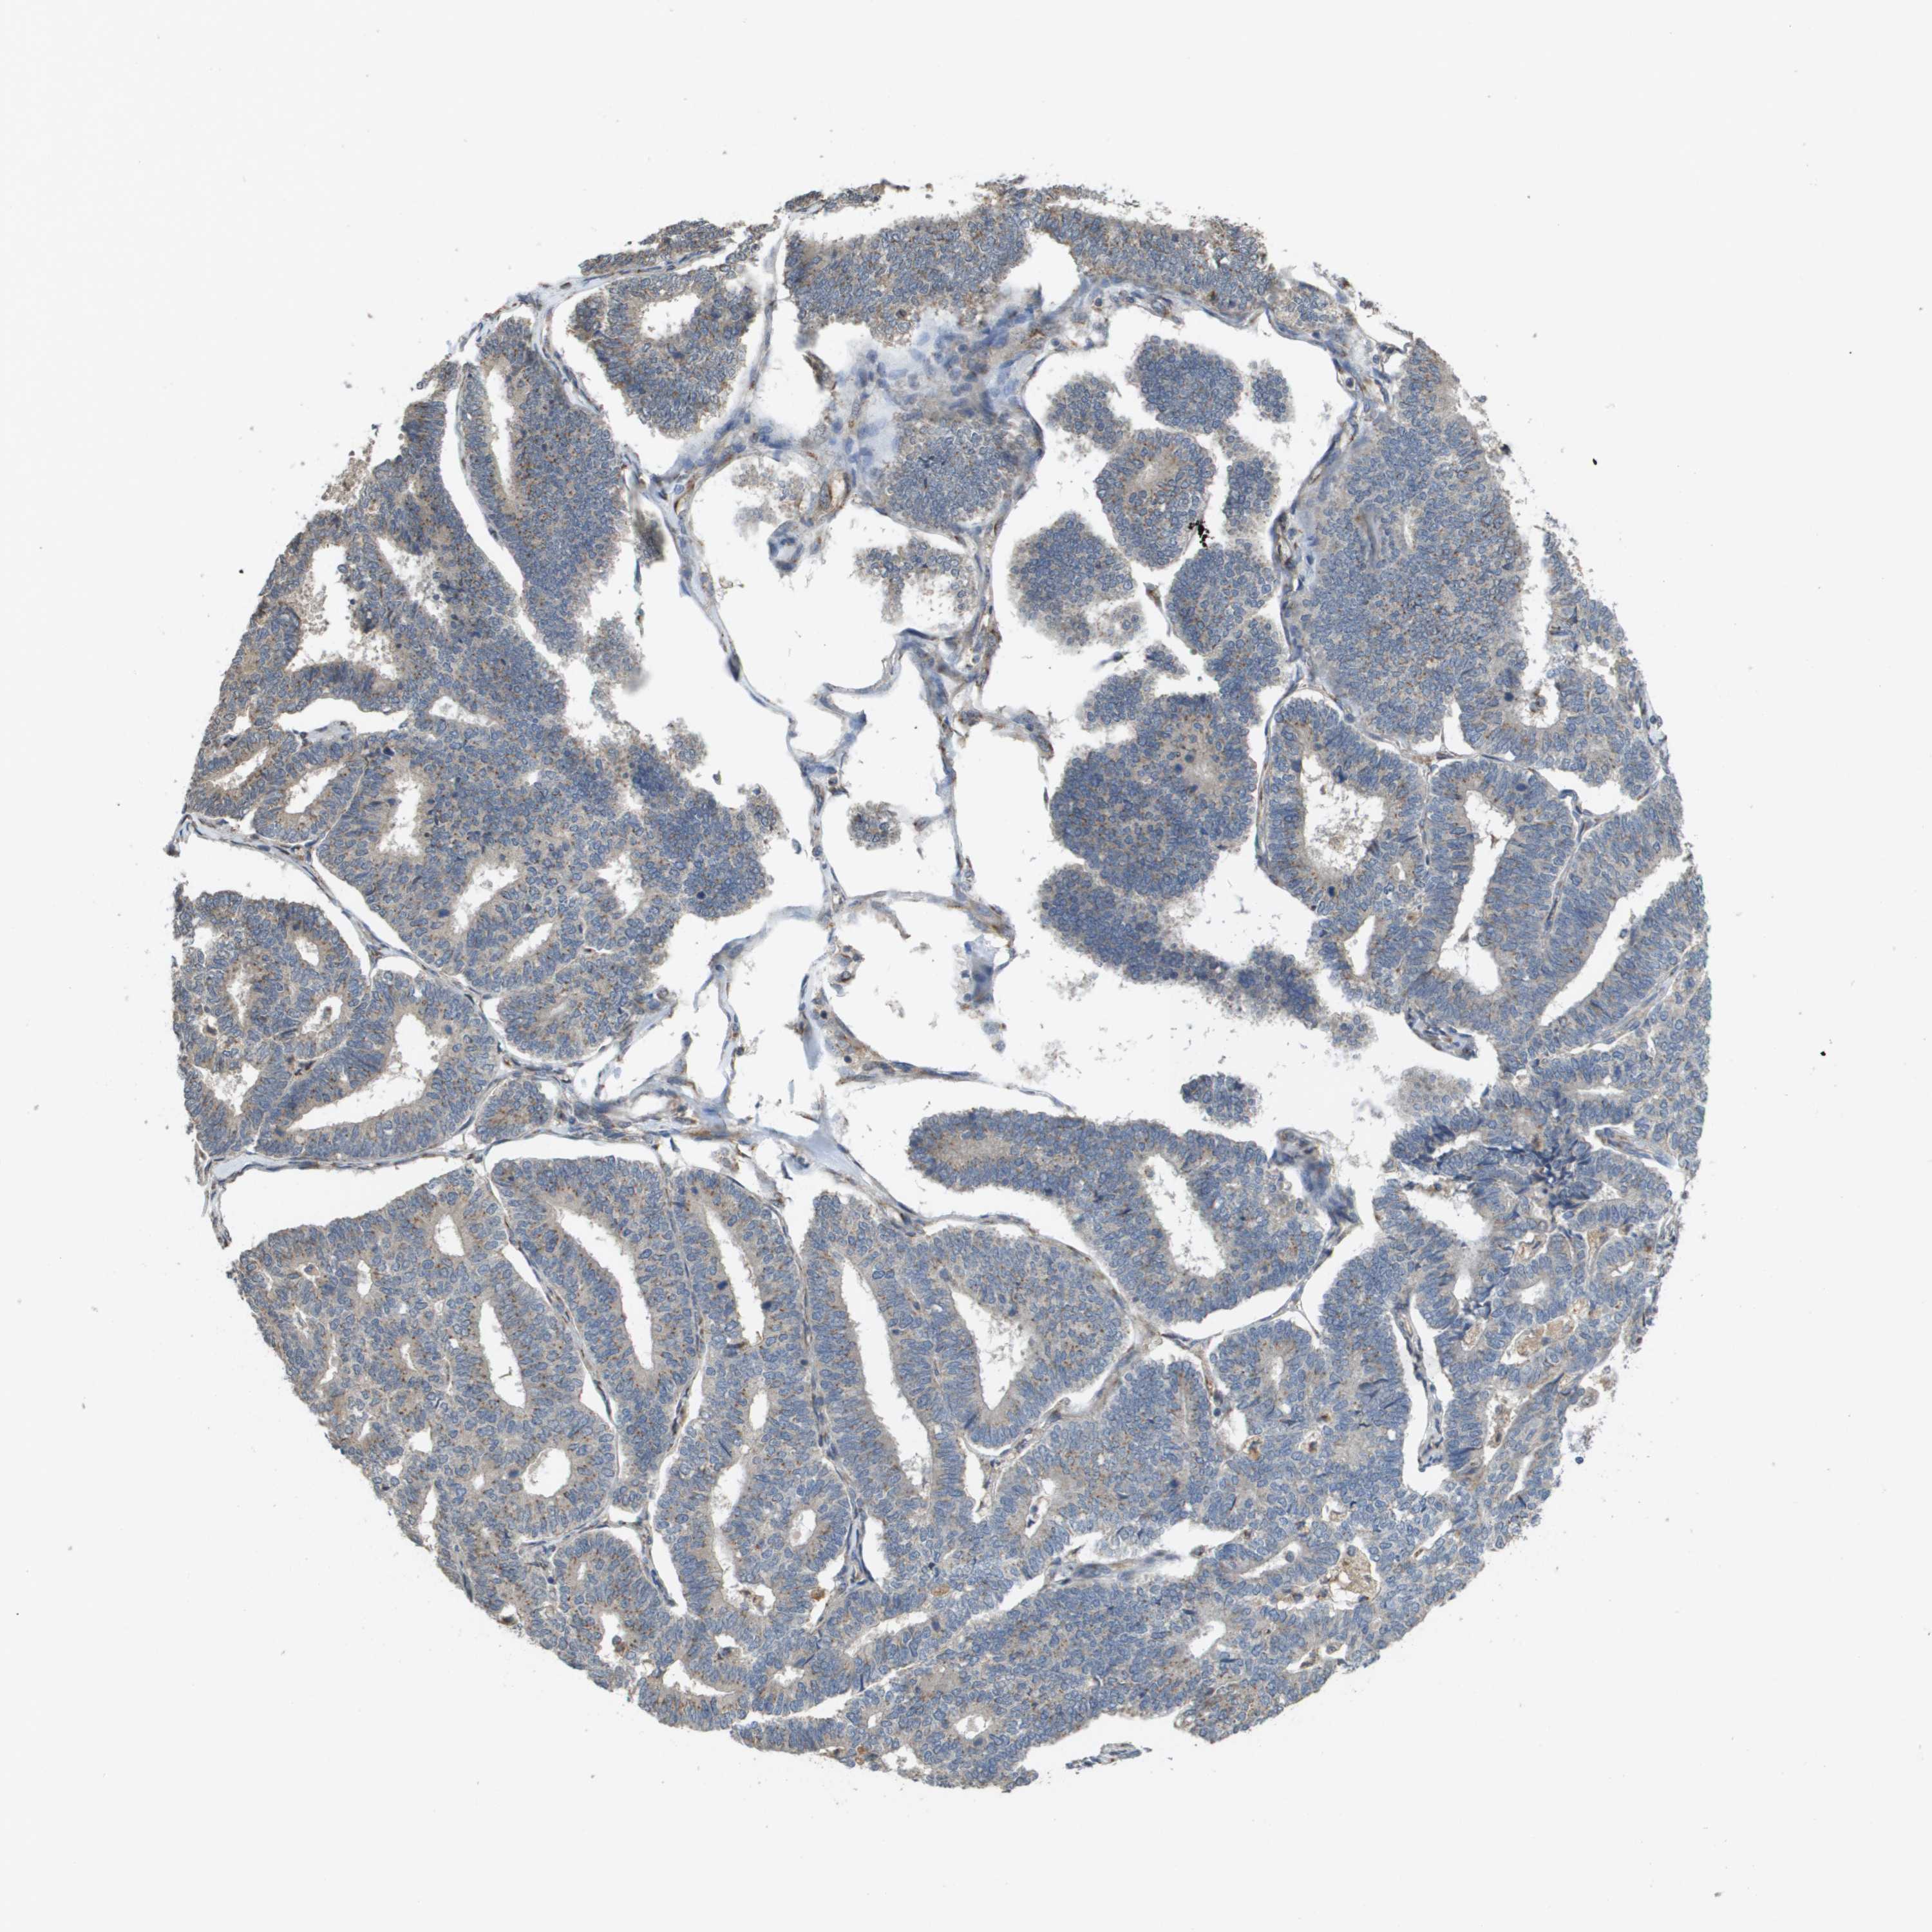

ENDOMETRIAL CANCER - Protein expressioni

A mouse-over function shows sample information and annotation data. Click on an image to view it in a full screen mode. Samples can be filtered based on level of antibody staining by selecting one or several of the following categories: high, medium, low and not detected. The assay and annotation is described here.

Note that samples used for immunohistochemistry by the Human Protein Atlas do not correspond to samples in the TCGA dataset.

Antibody stainingi

Antibody staining in the annotated cell types in the current human tissue is reported as not detected, low, medium, or high, based on conventional immunohistochemistry profiling in selected tissues. This score is based on the combination of the staining intensity and fraction of stained cells.

Each image is clickable and will lead to virtual microscopy that enables deeper exploration of all samples and also displays staining intensity scores, fraction scores and subcellular localization as well as patient and tissue information for each sample.

Antibody HPA006277

Antibody HPA006507

Antibody CAB017027